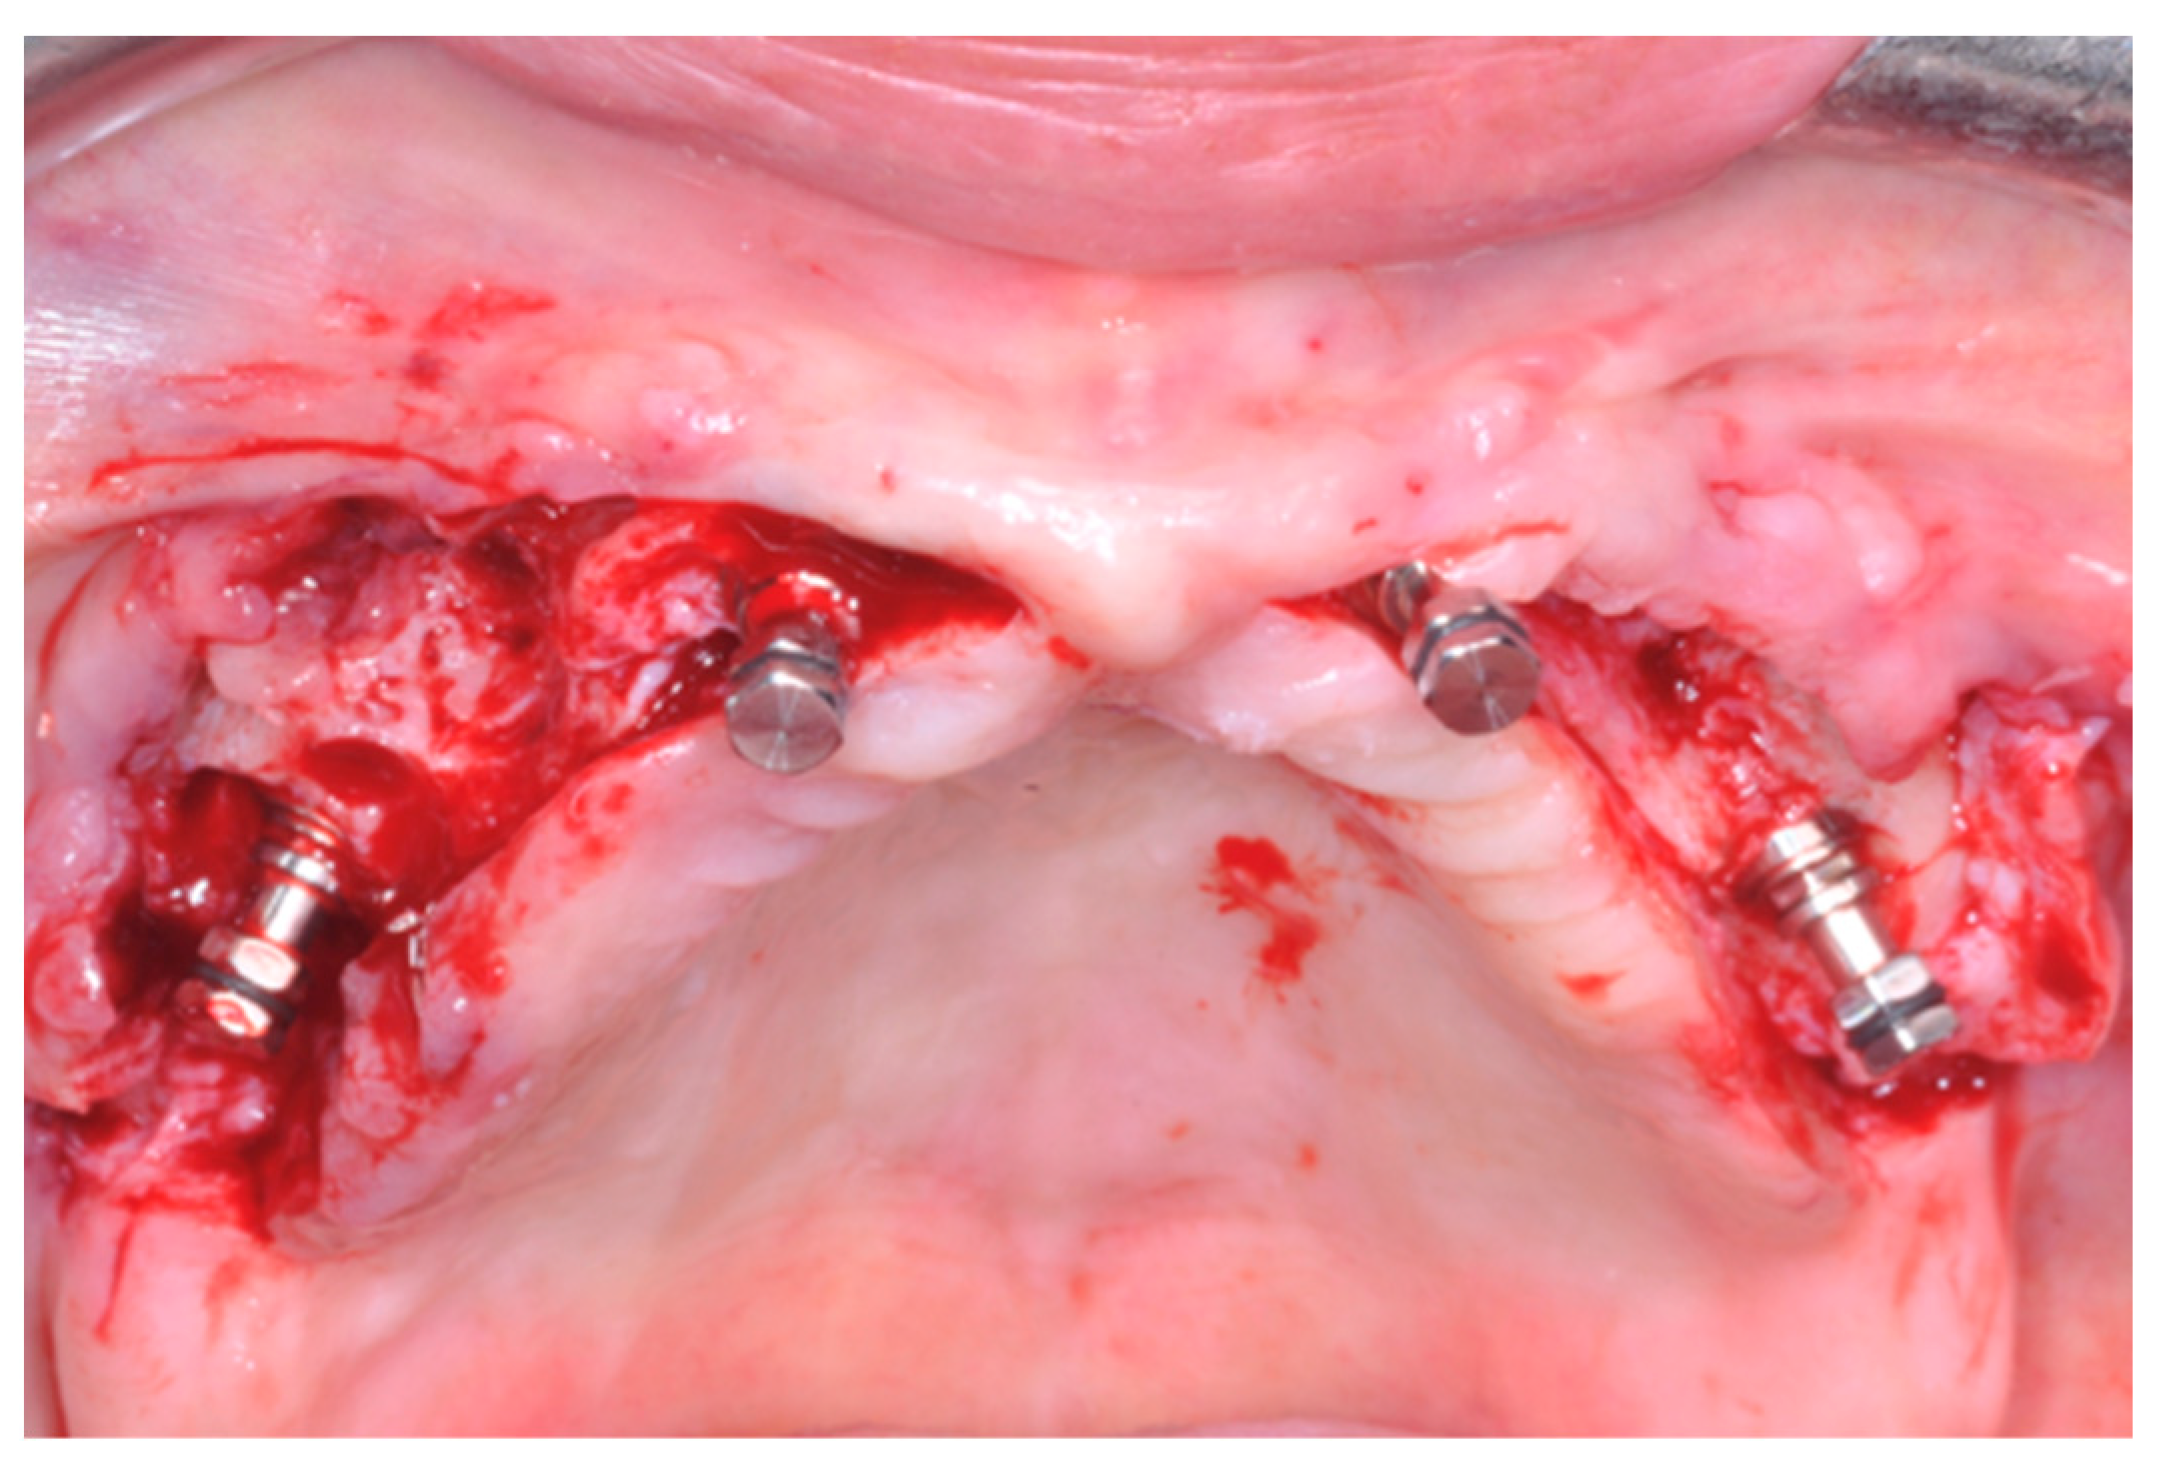

When present, residual teeth/roots were carefully extracted to minimize damage to the buccal plate, and sites were thoroughly cleaned from all granulation tissue. SPI-Contact (Thommen Medical; Grenchen, Switzerland) conical–cylindrical implants with a smooth 1.5 mm long collar, 11 mm in length, and 4.5 mm in diameter were inserted. Implants were placed following the protocol suggested by the manufacturer, except for the use of a 4.0 mm profile drill in order to underprepare the sites thus achieving a higher insertion torque. However, in a small number of patients (10%) Anyone (MegaGen Implant, Gyeongbuk, South Korea) implant 4 × 11.5 mm were placed. In case of anatomic limitation, distal implants were distally tilted in the premolar areas (Figure 1) [24].

Implants were placed with the 1.5 mm polished neck in a supracrestal position, also in the case of post-extractive implants. They were inserted with a torque of 70 Newton/cm and, once the motor stopped, implant stability was confirmed manually using the SPI-MONO torque ratchet (Thommen, Grenchen, Switzerland). If one of the four implants could not be placed with a minimum torque of 35 Ncm, a fifth implant was added near to the implant which did not achieve the required torque [25]. If two or more implants could not achieve a torque above 35 Ncm, implants were submerged and loaded conventionally after 3 months [26].

Figure 1. Four implants were placed, the distal ones being distally tilted.